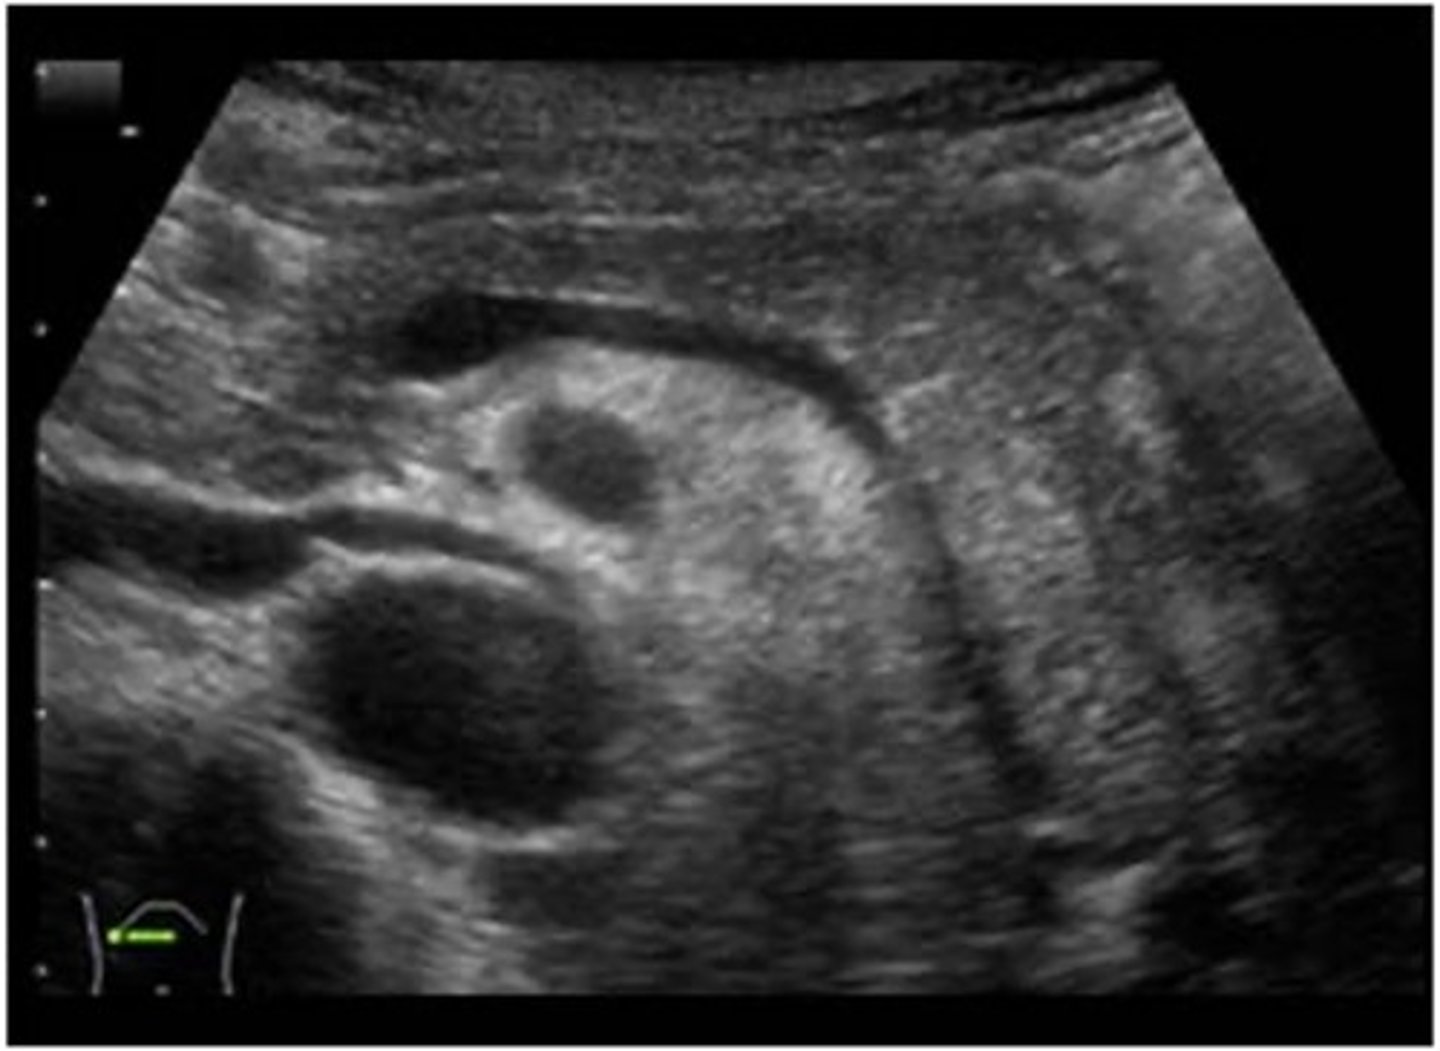

Right lobe of liver and hepatic veins on US

right lobe of liver and kideny on US

Portahepatis and bile duct on US

Normal